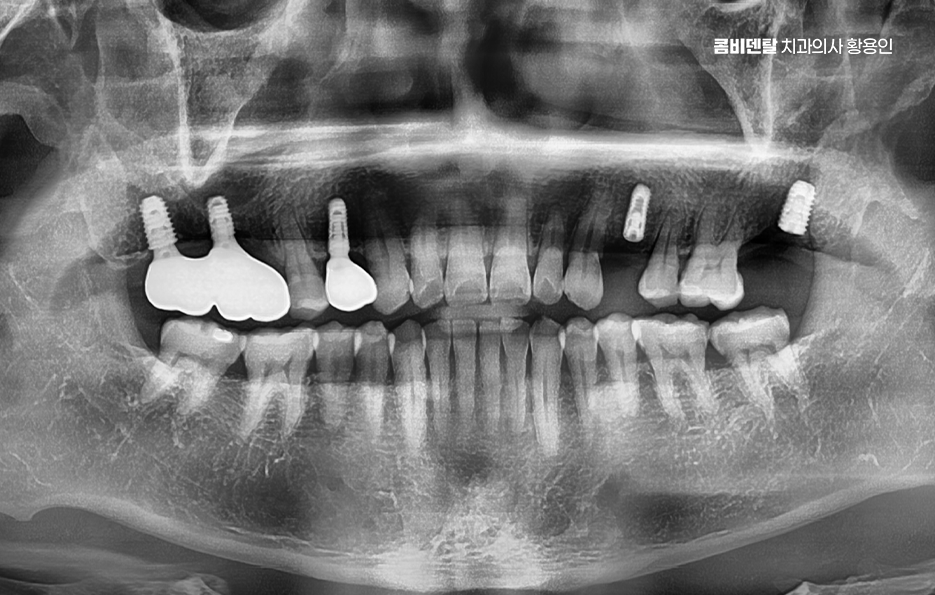

이처럼 치아 상실 후에 임플란트에 대한 중요성을 느끼게 되는 것은 특히 앞니라면 인상을 좌우하는 위치이기 때문에 미루는 경우가 거의 없지만 어금니의 경우 반대편으로 씹으면 되지 않을까 하면서 치료를 미루는 경우가 많지만 어금니 없으면 얼굴 발음 및 편측 저작으로 인한 반대편 치아의 문제, 잇몸 뼈의 흡수 등 여러 문제로 이어질 수 있는데요

어금니는 단순히 음식을 씹는 역할만 하는 게 아니며 우리 턱과 얼굴을 지탱해주는 일종의 기둥 같은 존재로서 특히 아래 어금니는 턱뼈에 직접 연결되어 있어서 이 부분이 빠지면 턱뼈 자체가 빠르게 흡수되기 시작하고 뼈는 자극이 있어야 유지되는데 어금니가 없어진 자리엔 씹는 자극이 사라지니까 뼈가 점점 가라앉는 거예요.

더 심각한 건 치열 전체가 무너지는 것으로 어금니가 빠지고 그 자리를 비워 두면, 위에 맞물리는 치아가 점점 내려오거나, 옆 치아가 쓰러져 들어가며 이렇게 정출된 치아는 다시 제자리로 돌아오지 않기 때문에, 나중에 임플란트를 하려고 해도 공간이 맞지 않아서 교정치료를 먼저 해야 할 수도 있었어요.

그래서 이런 문제들을 막기 위해서라도 임플란트는 어금니 상실 후 중요한 치료 옵션으로서 임플란트는 빠진 치아의 뿌리 역할까지 해주기 때문에, 단순히 공간을 채우는 게 아니라 턱뼈에 자극을 줘서 뼈 흡수를 막아주고, 위아래 치아가 정상적으로 맞물릴 수 있게 해주며 다른 보철 방식과 비교해도 장기적인 안정성과 기능 회복 면에서 유리한 거예요.

임플란트를 빨리 하는 게 좋은 이유는, 시간이 지나면서 턱뼈가 점점 흡수돼버리면 임플란트를 심을 뼈 자체가 부족해지는 상황이 생기기 때문이며 이때는 뼈이식이나 상악동 거상술 같은 추가 수술이 필요하게 되고, 치료 기간도 길어지고, 비용도 많이 올라가기 때문에 어금니가 빠졌다고 방치하는 시간만큼 치료는 더 복잡해질 수 있다는 점에서 어금니 없으면 얼굴 발음 및 오늘 알아본 것처럼 다양한 문제로 이어질 수 있음을 잘 이해하여 빠르고 나에게 맞는 치료 계획을 세우시고 장기적으로는 수명 유지까지 잘 고려하여 치료 계획을 잘 세워보시길 바라고 있어요